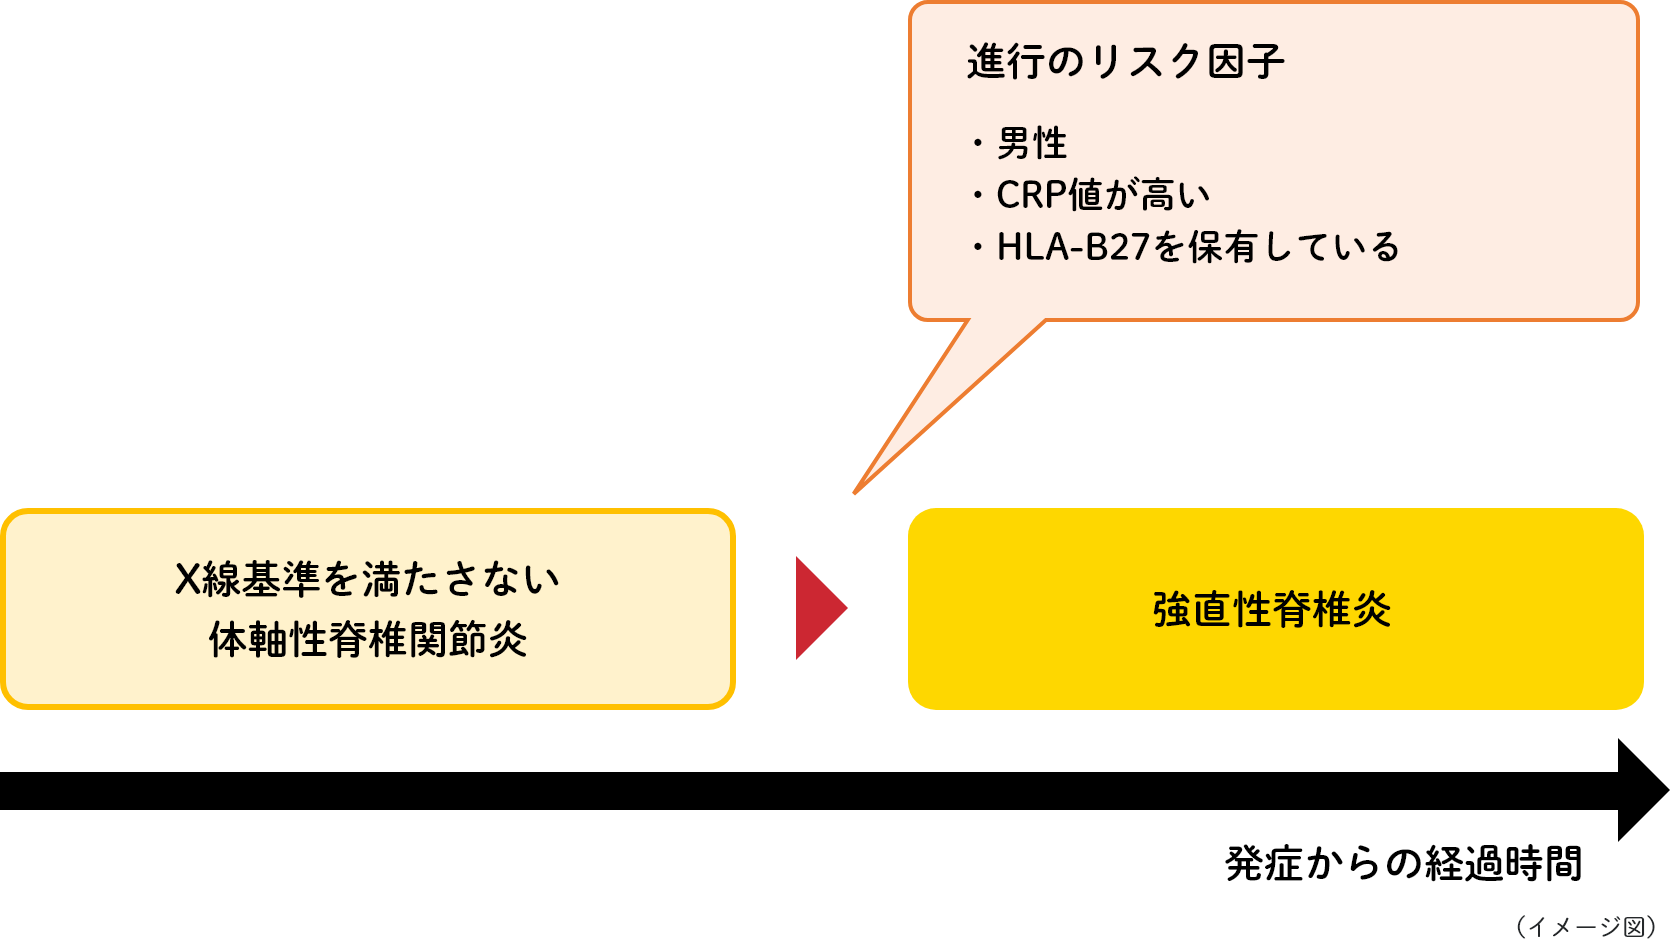

椎骨の硬直を引き起こす炎症の原因は不明です。ただし、遺伝的要因が関与していると考えられています。炎症を起こした椎骨が余分な骨を生成すると、それらは最終的に融合します。この融合は衝撃を吸収する脊椎椎間板を包み込み、脊椎の柔軟性を大幅に制限します。椎骨が癒合すると、「竹の背骨」と呼ばれることもあります。